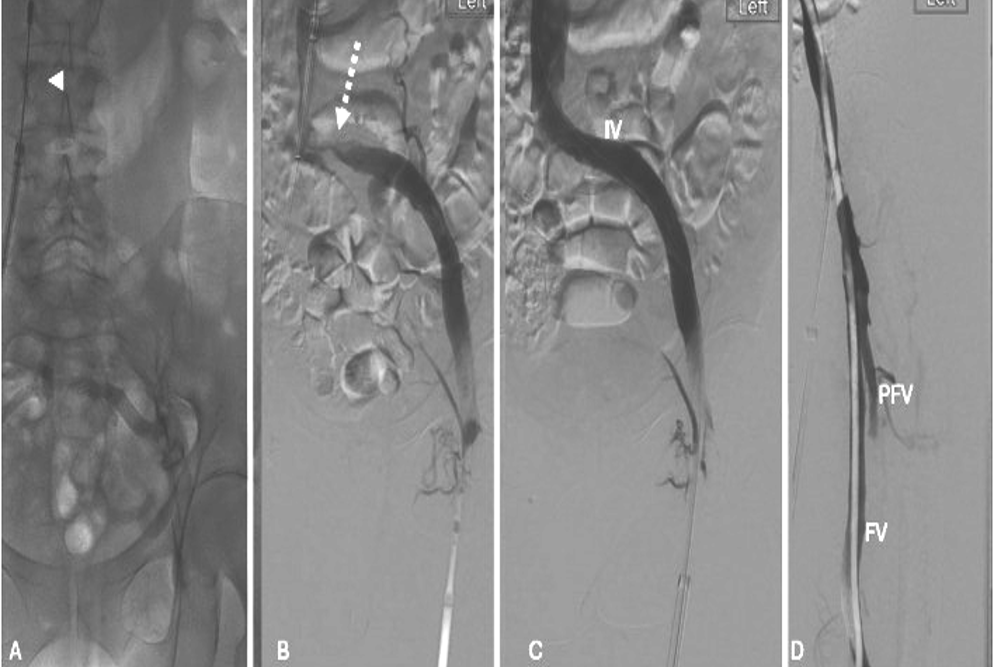

A. CT显示IVC(白色箭头)中血栓的近端范围, |

B. 右下肢浅表水肿(虚线箭头) |

术前低分子肝素,维持活化凝血时间>200秒

全麻下超声引导下,同侧大隐静脉和对侧股静脉插入16F鞘,静脉造影或腔内超声确认血栓范围。

通过同侧大隐静脉顺行血栓清除,使用Lightning Flash,并通过对侧股静脉提供临时下腔静脉栓塞保护。

将对侧CFV鞘推进到右侧髂静脉,同时将同侧鞘收回GSV(同侧大隐静脉)

通过股静脉CFV进行逆行血栓清除,涉及右侧CFV、FV、PFV和PV

14mm直径高压球囊进行血管成形

血管造影评估,顺行血流通畅

使用右大隐静脉(GSV)和对侧左股静脉(CFV)的右下肢血栓切除术的双入路技术。